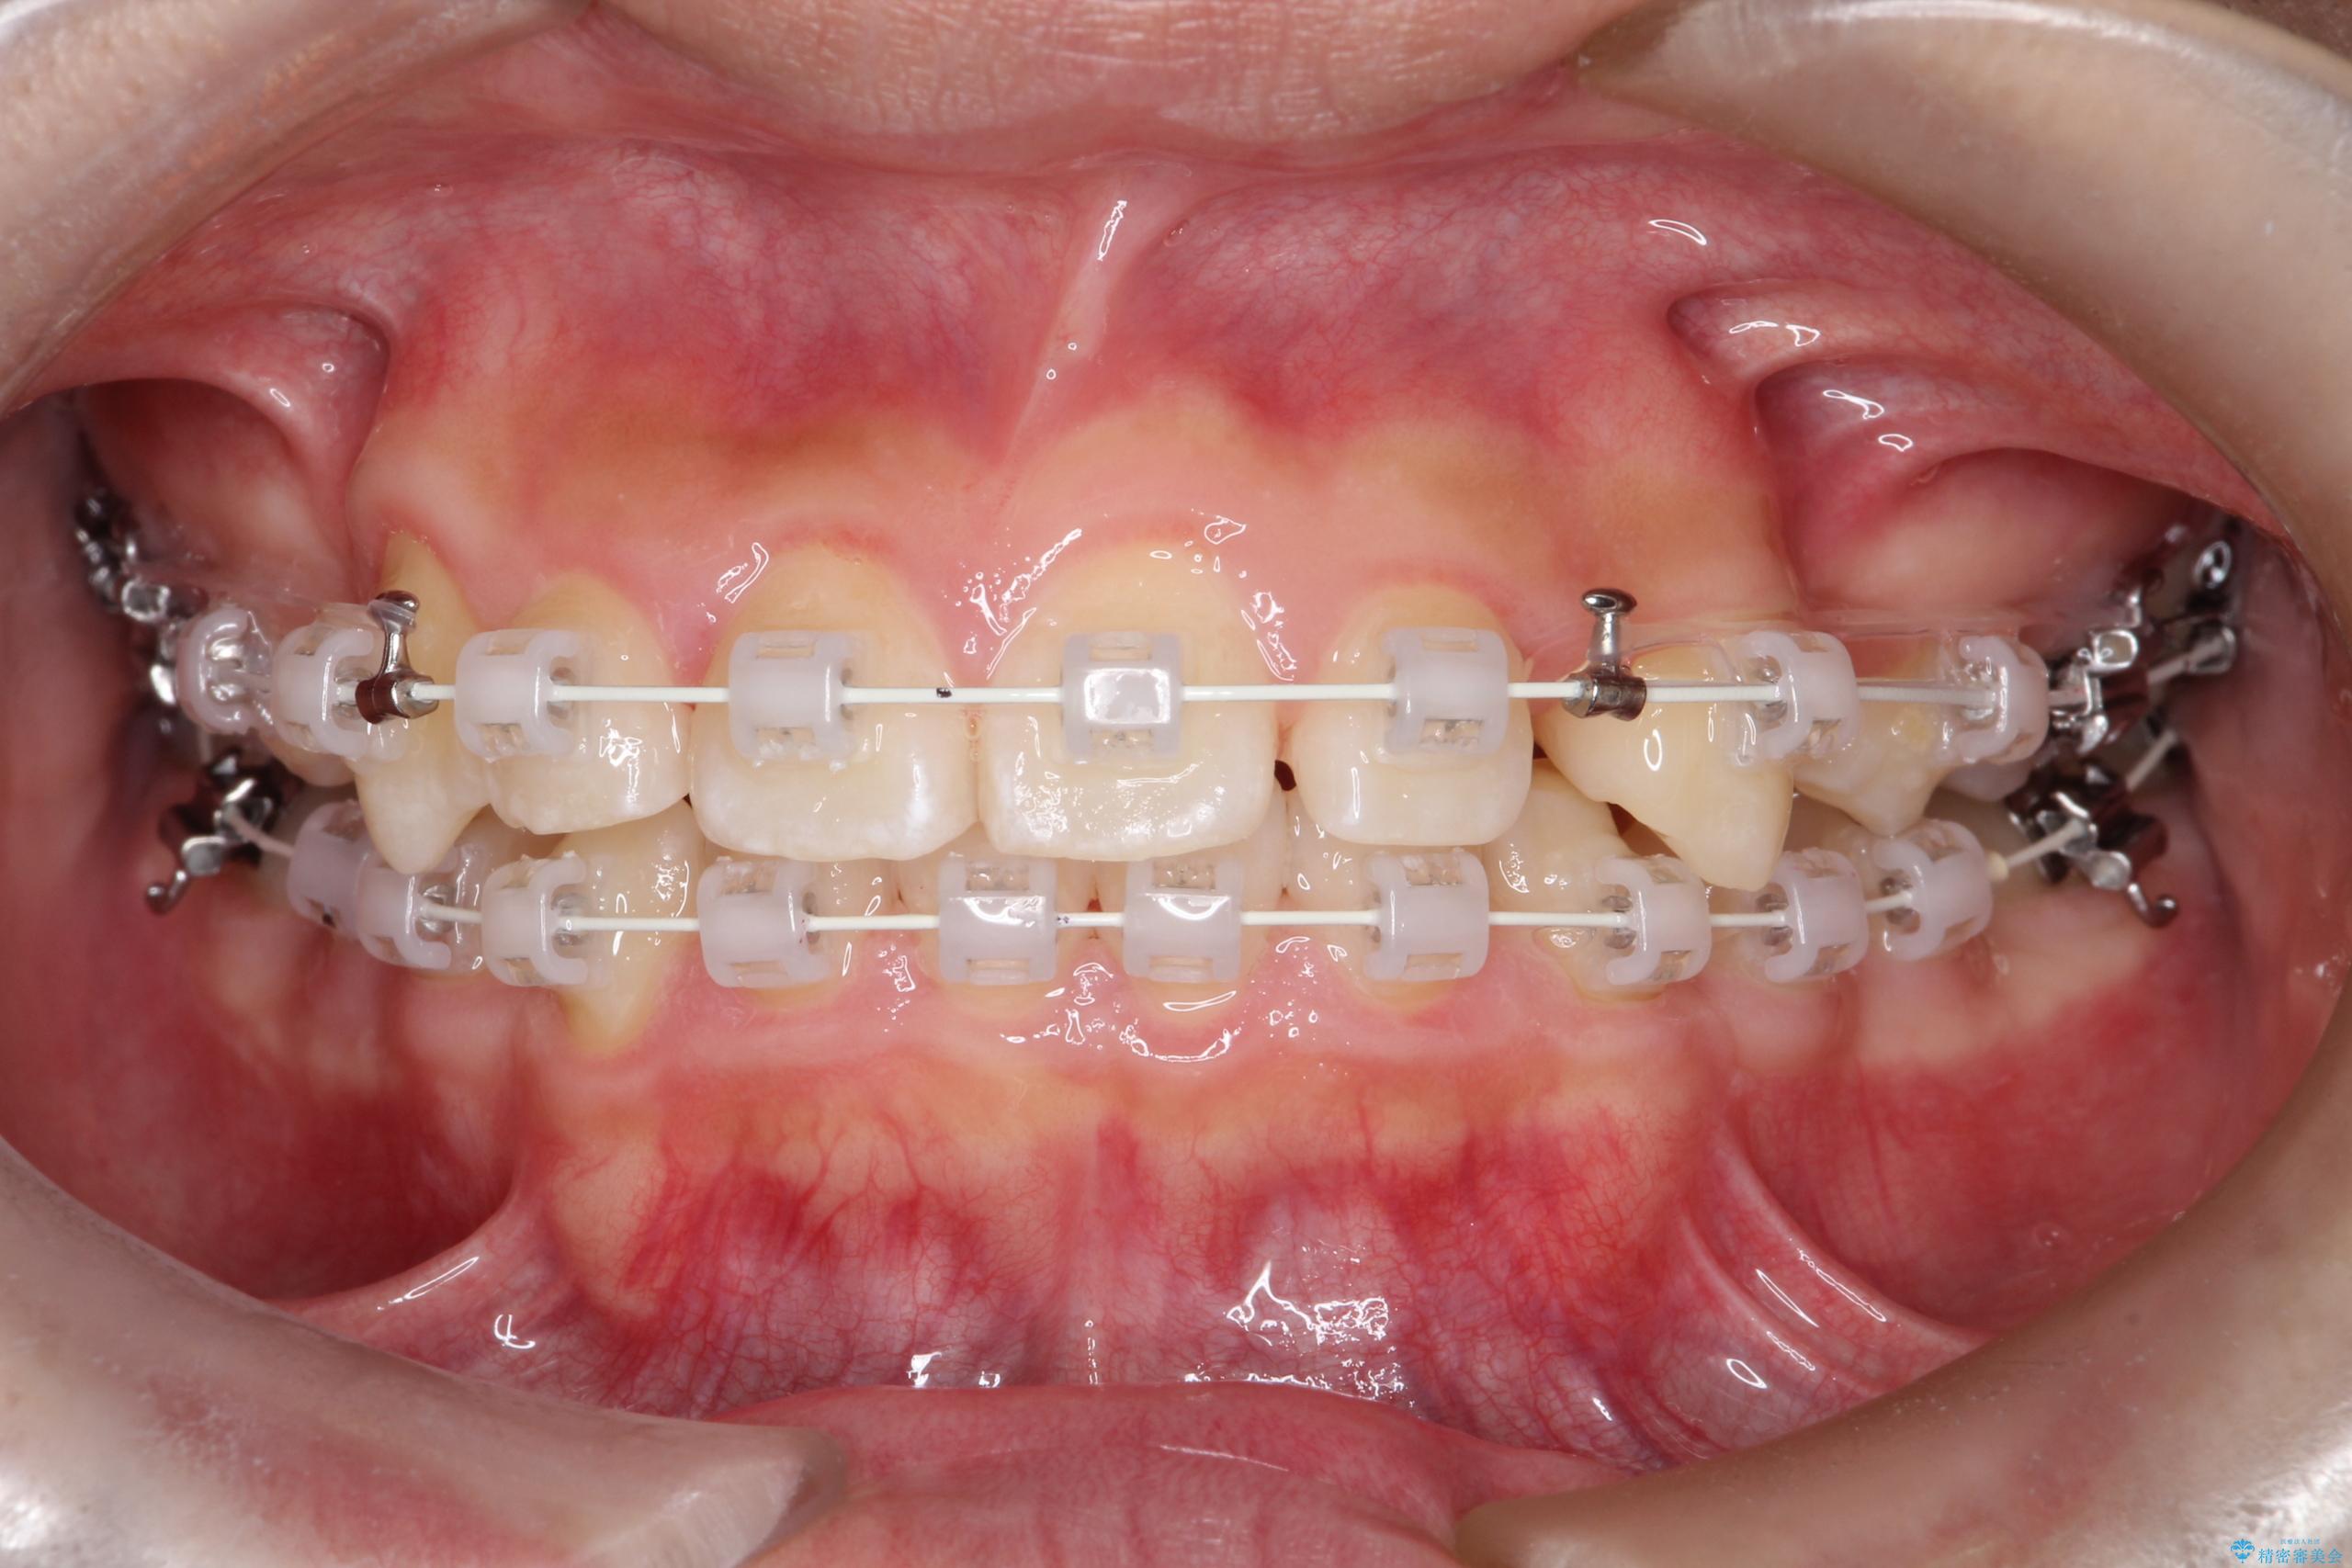

八重歯・歯並びのデコボコとディープバイトを改善した抜歯ワイヤー矯正症例

- ワイヤー(審美装置)

矯正の精密検査の結果上顎左右4番の計2本を抜歯し、審美性に配慮したワイヤー矯正装置(審美装置)を用いて治療を行いました。

八重歯などの歯列のデコボコが綺麗に改善され、患者様にも大変喜んでいただけました。また、咬み合わせが深い「ディープバイト」も併せて改善し、見た目だけでなく機能面でもバランスの取れた咬合を獲得しています。